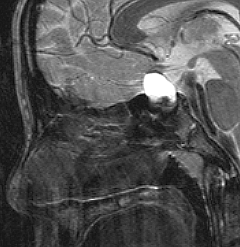

ちょっと大きな頭蓋咽頭腫です

嚢胞(液体が入っている袋)の部分と,腫瘍細胞が固まっている実質部分が入り交じっています。このくらいの大きさになってしまうと,下垂体機能を残すことはとても難しくなります。視神経が圧迫されて視力低下と視野障害を生じます。第3脳室が腫瘍で閉塞していて水頭症になっていますから知能の活動が低下します。

腫瘍を摘出するのに危ないのは,脳の血管の損傷です。左では白く,右では黒く線状に移っているのが太い脳動脈です。これら以外にもたくさんの細い重要な動脈が絡んでいます。

幸いこの患者さんの腫瘍は摘出できて患者さんは元気になりました。でもこのくらいのサイズになると手術がいつもうまくいくとは限りませんし重大な障害が残ることもあります。